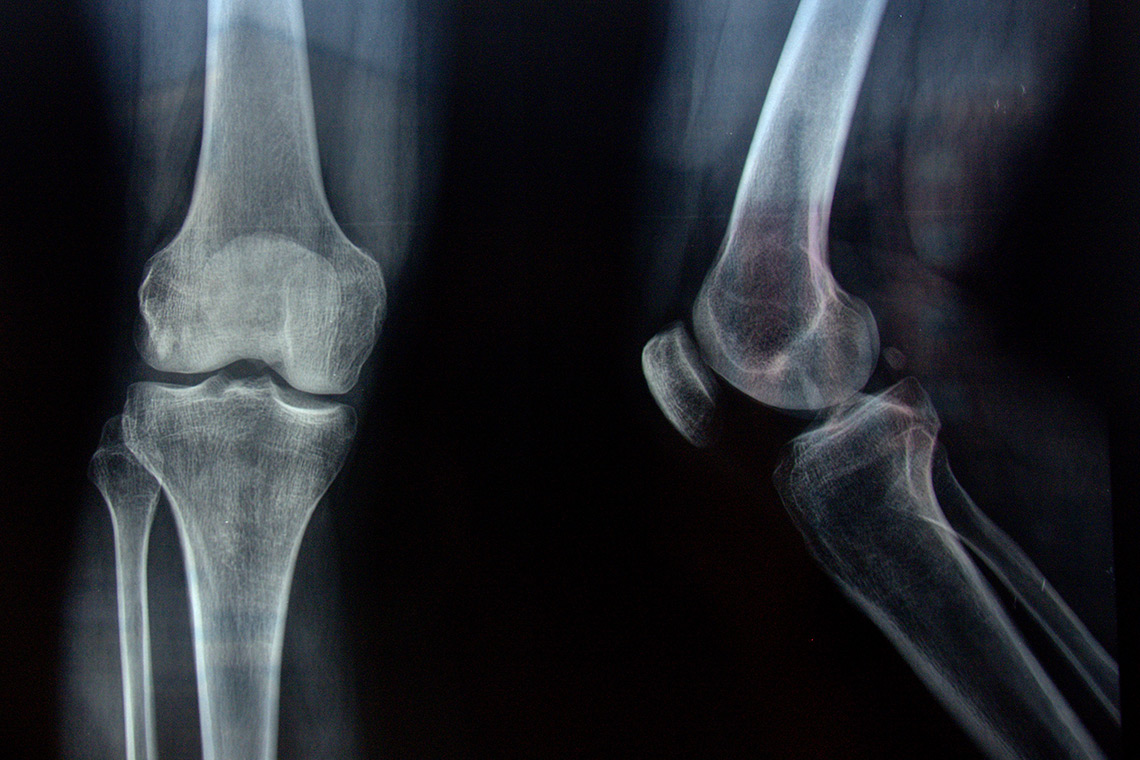

The study, done in collaboration with Eric Shattuck, an assistant professor at the University of Texas at San Antonio, looked at bone health data from 3,243 participants in the U.S. National Health and Nutrition Examination Survey. They found that sexual orientation was associated with disparities in bone mass across the spine and femur, the areas in which bone mineral density was measured as part of the survey. The finding was independent of known risk factors for poor bone health such as tobacco use, alcohol consumption and illicit drug use.

Bone mineral density is an important measure of bone strength, with minerals like calcium and phosphorus playing a vital role in bone strength. Gibb says those with higher bone mineral content generally have stronger bones, while lower bone mineral density results in weaker bones. That puts the the latter group at a greater risk of fracture.